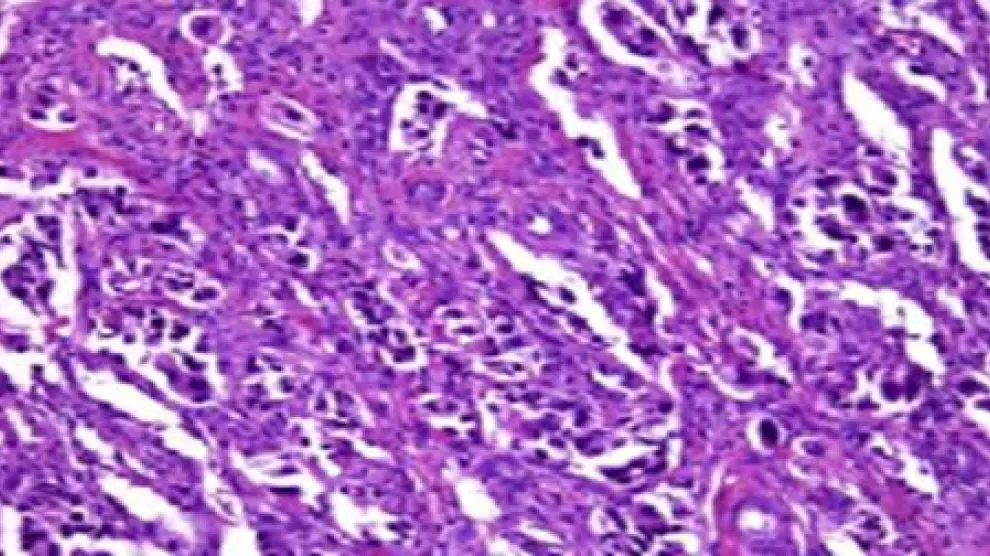

La investigación 'Epigenetic profiling to classify cup: a multicentre, retrospective analysis', publicada en la revista 'Lancet Oncology', fue realizada a partir del estudio de marcadores de metilación del ADN de 38 tipos de tumor y sus correspondientes metástasis con un banco de 10.500 muestras, con lo que se convierte en el estudio con mayor número de casos que se ha desarrollado en la literatura médica en este campo.

El resultado del test proporciona una información diagnóstica complementaria a otras pruebas -anatomía patológica, diagnóstico por la imagen, entre otros- realizadas con técnicas convencionales que permiten diagnosticar únicamente el 25% del cáncer, mientras que la herramienta desarrollada alcanza el 87% del diagnóstico.

Los CUP son un grupo heterogéneo de cánceres en estadio avanzado de la enfermedad, es decir con metástasis, y de mal pronóstico.